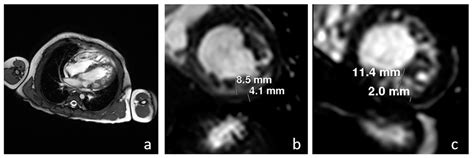

To better understand Non Compaction Cardiomyopathy, it is helpful to visualize the heart's anatomy. Typically, the heart walls are smooth and dense. In patients with NCCM, the myocardium (the heart muscle) remains thin and features excessive trabeculations—small, finger-like projections—and deep inter-trabecular recesses. These structural flaws create a "spongy" appearance when viewed through imaging techniques.

Diagnosing Non Compaction Cardiomyopathy primarily involves advanced cardiac imaging. Physicians utilize specific diagnostic criteria to differentiate NCCM from a normal heart that may just have prominent, yet healthy, trabeculations.

Cardiac MRI Considered the gold standard for accurately measuring myocardial thickness.